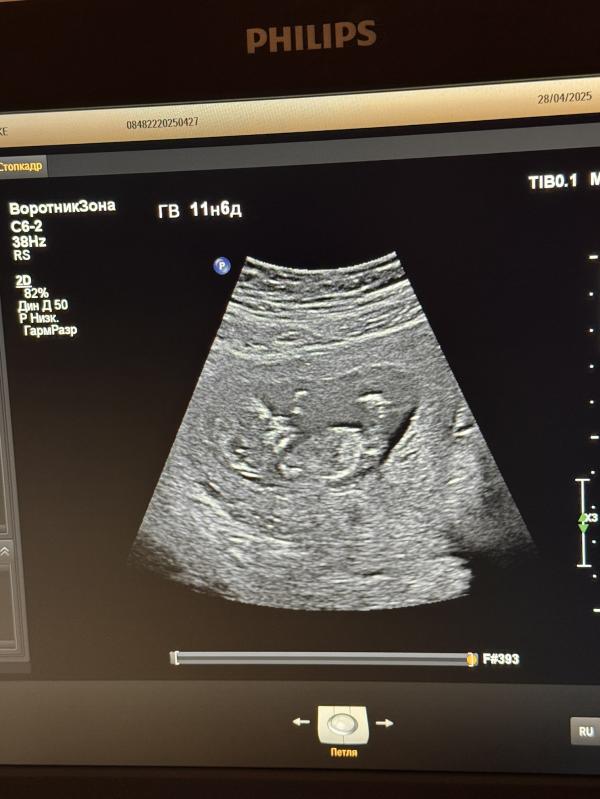

Я сходила на первый скрининг, очень порадовалась, что срок по месячным 100% совпадает со сроком на узи ☺️

Все хорошо, креветочка 5,3см, всякие гадости и отклонения, к счастью, не обнаружены.